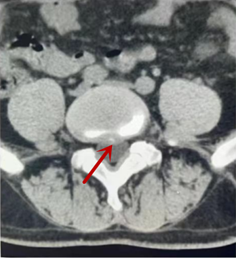

利器二:CT

CT利用X射線對(duì)人體檢查部位通過(guò)電腦切成若干層掃描,然后把每層的圖像都能顯示出來(lái)。CT相對(duì)于X光片具有更高的密度分辨力,可直接顯示X線片無(wú)法顯示的病變,觀察腰椎有無(wú)微小的骨折、骨質(zhì)有無(wú)破壞等骨質(zhì)情況、以及腰椎間盤突出、腰椎神經(jīng)根、椎管、椎間小關(guān)節(jié)的情況等。同時(shí)還可以通過(guò)后處理,重建腰椎矢狀位或冠狀位圖像,形成腰椎的3D圖像,更直觀地觀察病變部位,對(duì)腰椎手術(shù)風(fēng)險(xiǎn)具有提示作用,對(duì)手術(shù)方式的選擇具有指導(dǎo)意義,但是對(duì)神經(jīng)、脊髓損傷程度的顯示不如MRI,軟組織的分辨率仍有一定限制,對(duì)椎管內(nèi)病變顯示欠佳,且有一定的輻射。

箭頭提示椎間盤突出

從左向右依次為CT矢狀位重建圖像、三維重建圖像、軸位掃描圖像,箭頭提示腰1椎體爆裂性骨折